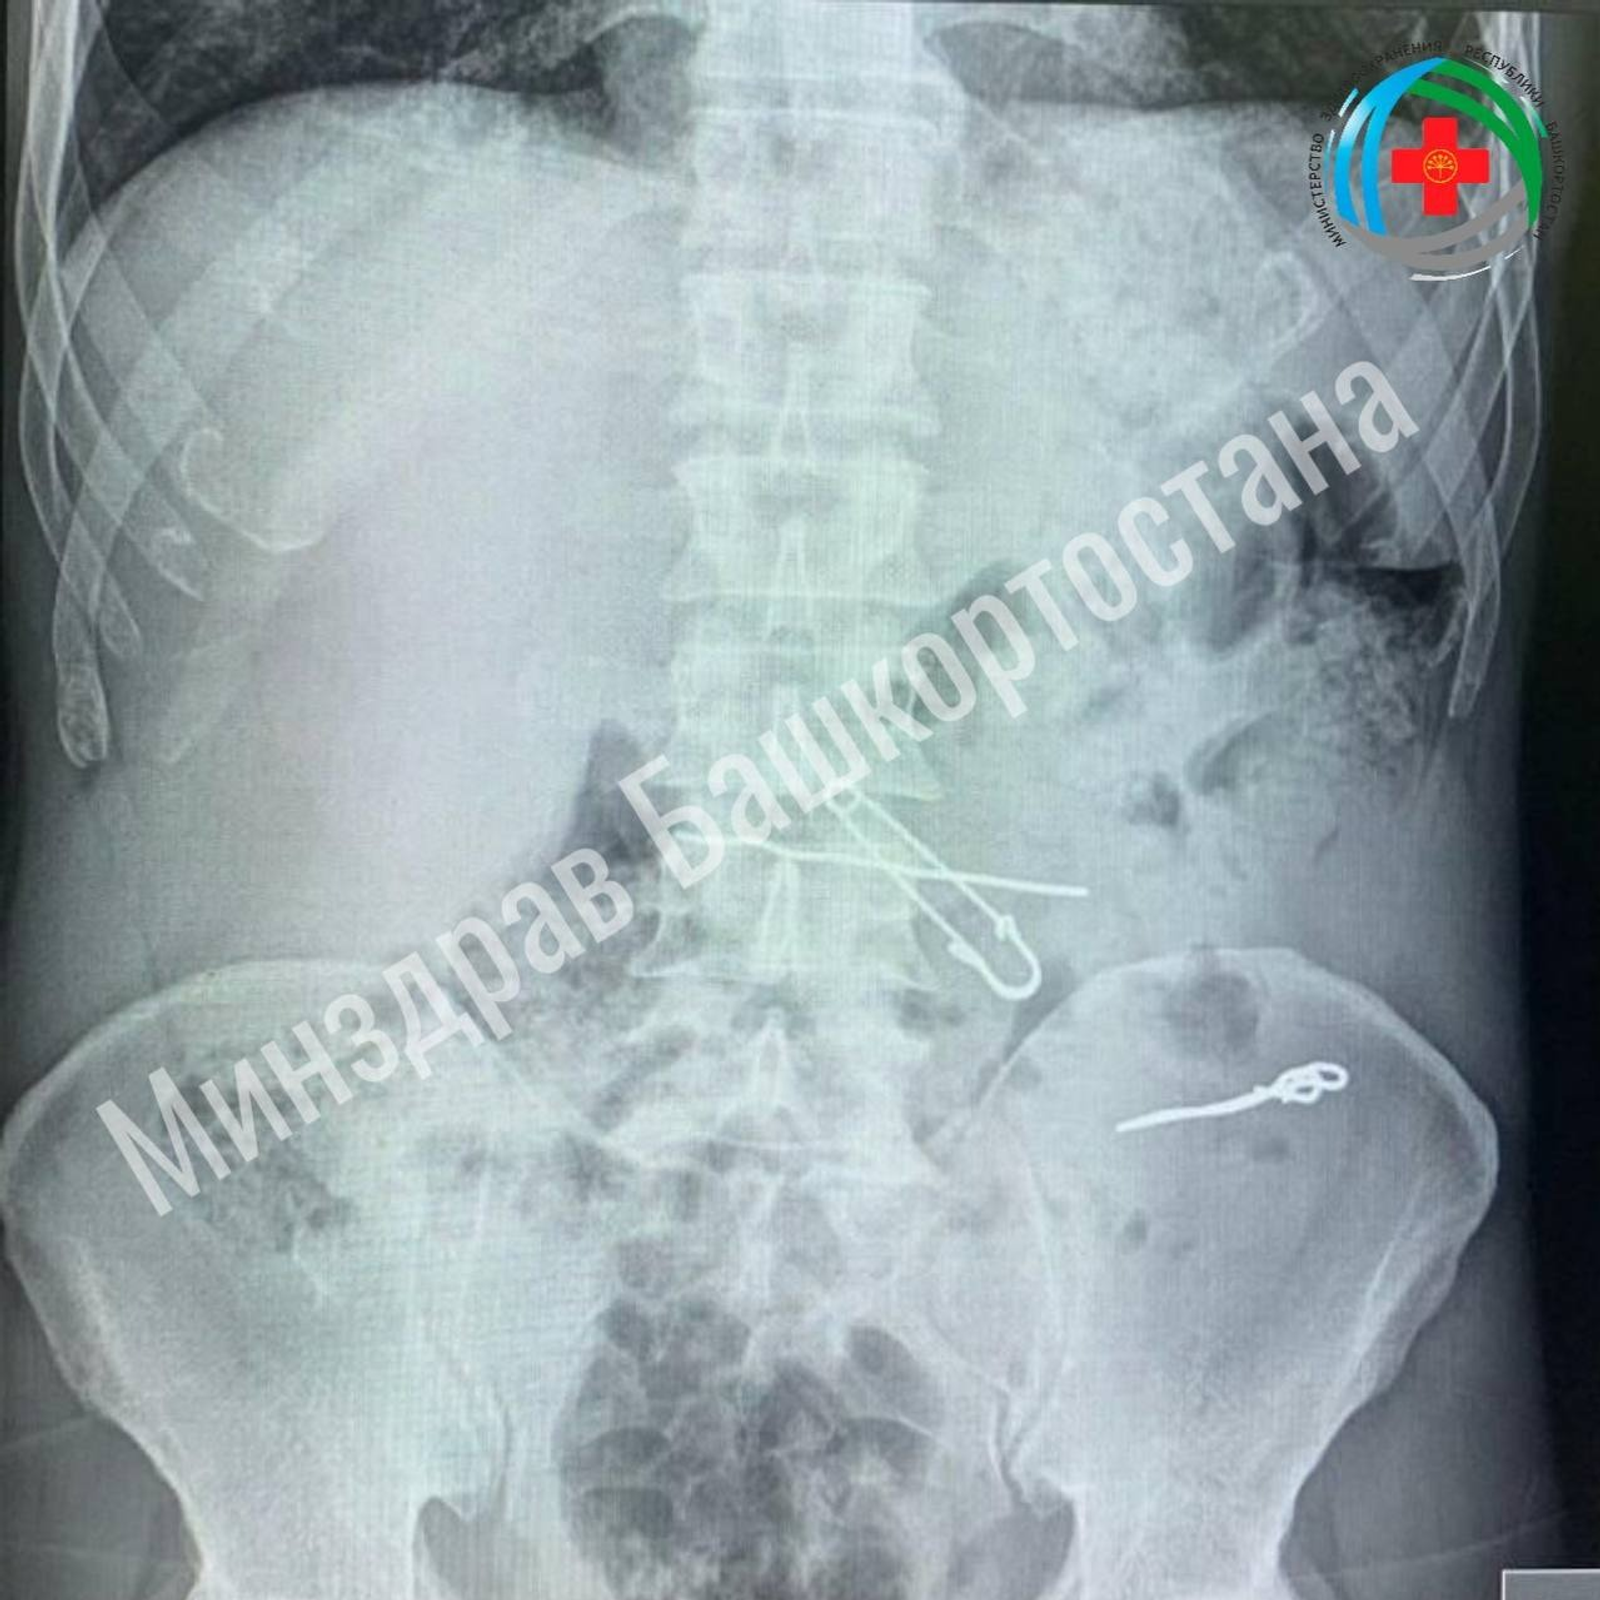

Как сообщил в своих соцсетях министр здравоохранения РБ Айрат Рахматуллин, пациент обратился в приемный покой медучреждения с жалобами на боли в животе. По результатам обследований в толстой кишке у него обнаружили проволоки, скрепки длиной 47, 62 и 90 мм. В желудке же находились булавка и проволока. Мужчину госпитализировали в отделение гнойной хирургии для оперативного лечения.

Хирурги провели операцию и удалили инородные тела. Во время хирургического вмешательства была проведена контрольная рентгенография.